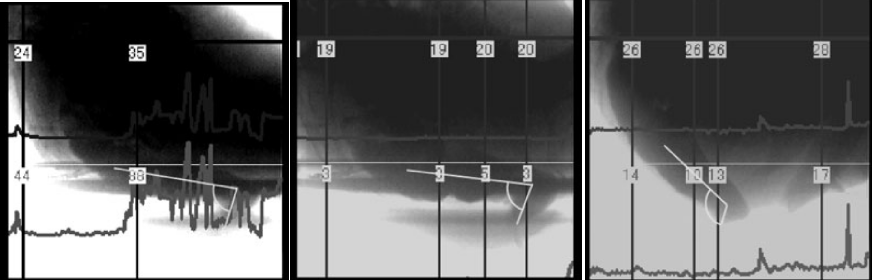

从左到右依次为坐姿、坐姿踩小板凳、蹲姿的直肠-肛门角,图片来源:参考文献2直肠-肛门角的角度越小,意味着直肠和肛门折叠得越厉害,而角度越大,意味着折叠程度越低。假如是 180 度,就意味着直肠和肛门成一条直线,便便可以畅通无阻地“倾泻而出”(不过这样的情况一般不会出现)。

而我们拉便便时候不同的姿势,也确实会影响这个直肠-肛门角的度数。2010 年发表在《下尿路症状》(Lower Urinary Tract Symptoms)上的一项研究,就找来了 6 名志愿者,研究了他们在 3 种拉便便姿态下的直肠-肛门角,这三种姿态分别是坐姿、坐姿外加脚踩小板凳、蹲姿。

结果发现,不同姿态下直肠-肛门角度之间确实存在差异。坐在马桶上,直肠-肛门角的平均度数为 100°,坐在马桶上踩着小板凳,平均度数为 99°,而在蹲姿状态下,这一度数平均值是 120°。所以,在这三种拉便便姿态下,蹲坑的姿态确实能够让“便便的通道”更顺畅。

为了更进一步研究三种姿态对拉便便的影响,研究者往实验者的直肠里注入了造影剂,让他们以三种不同的姿态进行模拟排便,并且记录这些姿态下腹部的压力。结果发现,在三种姿态下,坐姿状态下实验者需要额外施加的腹部压力最大,其次为坐姿踩着小板凳,在蹲姿状态下实验者需要额外施加的力最小。

不踩小板凳与踩小板凳,直肠-肛门角变化